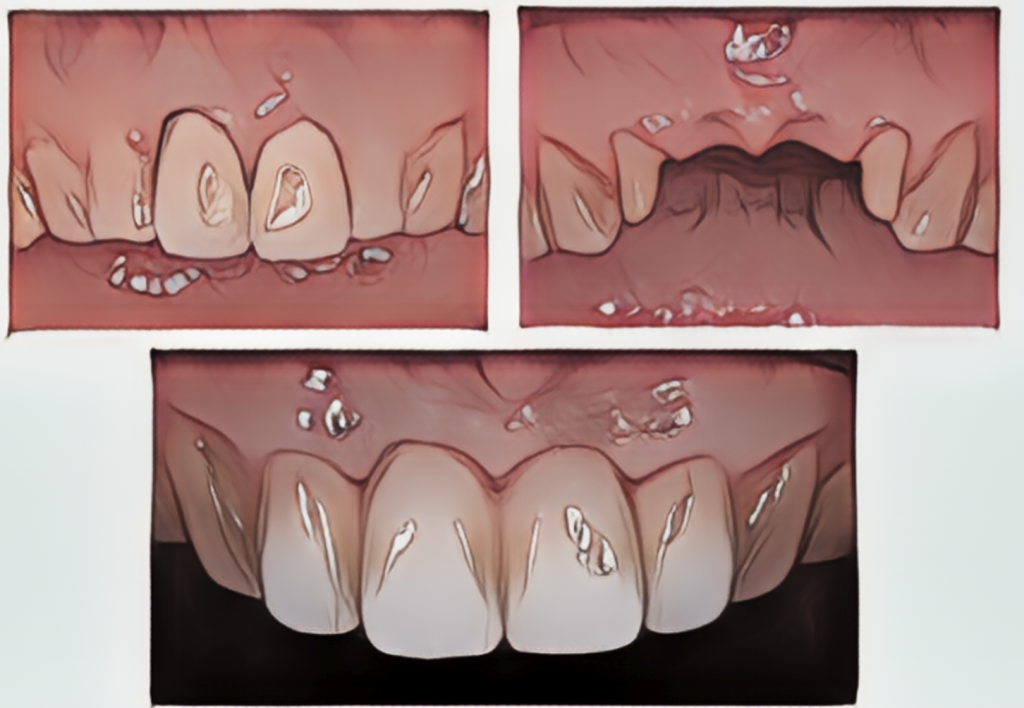

前歯に関しては、より高い審美性を求められることが多いので、次の症例のように透明感の高いジルコニアセラミックによるブリッジ修復を行うことが多いです。

患者様は60代女性。前歯がかぶせ物の中で割れてしまっており、抜歯後にジルコニアセラミックを用いたブリッジを行うこととなりました。

ジルコニアセラミッククラウン 14.3〜16.5万円/本(税込)

こちらはブリッジの土台となる歯は神経のない歯となりますが、このタイミングでインプラントを用いてしまうと、将来隣の神経のない歯が割れてしまった時に次の一手が非常に難しいものとなります。ご相談の上で、ブリッジによる治療を選択することになりました。